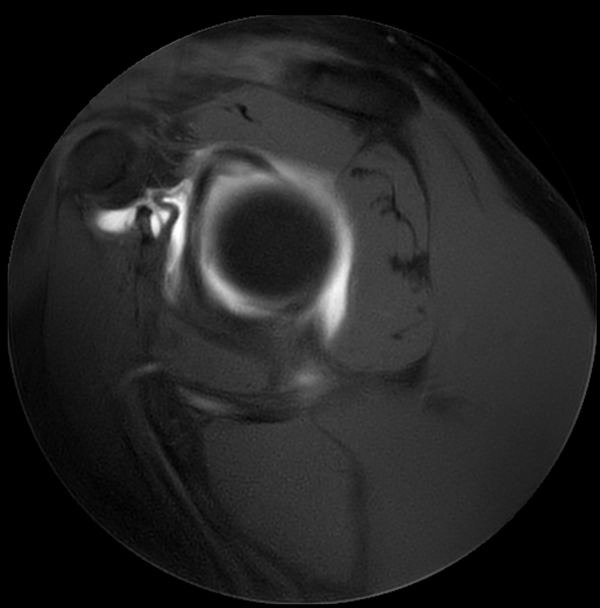

Axial MultiVane XD - T1w SPAIR